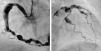

A 67-year-old Caucasian man with a medical history of ulcerative colitis and hypertension presented with chest pain and diaphoresis ongoing for 12hours. His physical examination was unremarkable; electrocardiography revealed inverted T waves in leads I, aVL and V4–V6, and troponin I levels were initially positive at 14.7ng/dl, reaching a maximum of 40.8ng/dl. Echocardiography showed hypokinesia of the lateral wall of the left ventricle and an ejection fraction of 0.51. Subsequent cardiac catheterization revealed diffuse three-vessel aneurysmal coronary artery disease without flow-limiting stenoses (Figure 1) and the image of a recanalized thrombus in the aneurysmal first diagonal (the culprit lesion).

Right and left coronary angiography showing severe diffuse aneurysmal coronary artery disease. (A) Selective right coronary angiogram in left anterior oblique view showing a large aneurysm involving the proximal and mid segments of the right coronary artery (maximum diameter 12mm) as well as multiple smaller aneurysms in the distal segment of the vessel and in the posterolateral branch. (B) Selective left coronary angiogram in right anterior oblique view showing multiple aneurysms involving the distal portion of the left main coronary artery (LMCA), the proximal and mid segments of the left anterior descending (LAD) coronary artery and the proximal segment of the circumflex and the marginal branch.